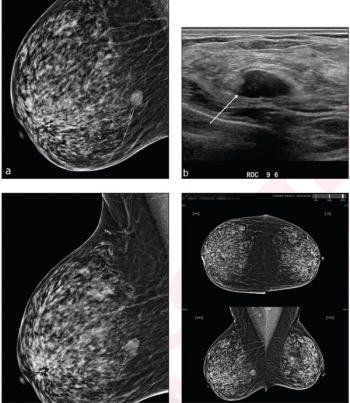

In a new study comparing standard breast MRI, abbreviated breast MRI and contrast-enhanced mammography in supplemental breast cancer screening, researchers found that MRI offered a greater than 14 percent higher cancer detection rate and a nearly 39 percent higher sensitivity rate than CEM.

In a study of over 1.300 women with dense breasts, the combination of mammography and ultrasound had a recall rate of 11.7 percent, a specificity rate of 89.1 percent and an accuracy rate of 89.2 percent in comparison to a 21.4 percent recall rate, 79.4 percent specificity and 79.5 percent accuracy for the combination of mammography, ultrasound, and artificial intelligence (AI).